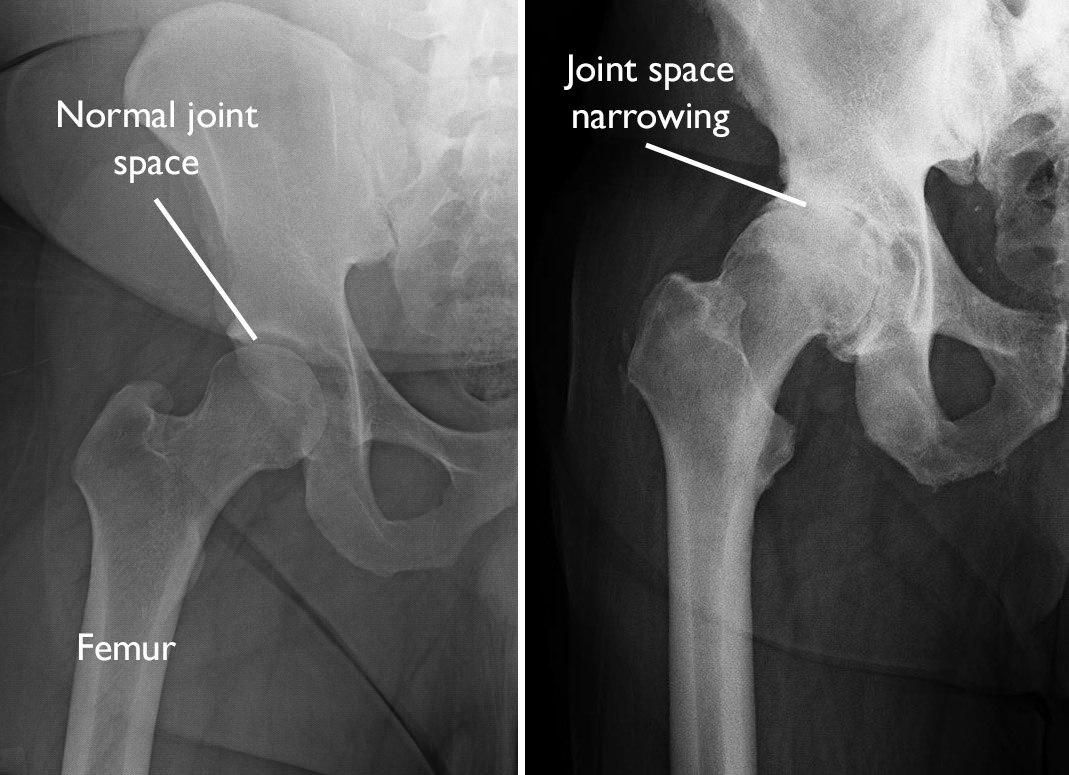

Arthritic Hip Joint Xray The diagnosis of oa is based on a combination of radiographic findings of joint degeneration. Osteoarthritis (oa) of the hip is the most common form of joint disorder of the hip, affecting primarily the articular cartilage of the. The diagnosis of oa is based on a combination of radiographic findings of joint degeneration. Osteoarthritis (oa) is the most common disease of the hip joint seen in adults. Osteoarthritis of the hip can be graded according to its severity. Minor wear and tear of the hip joints and minor bone spurs, often with little to no pain. Osteoarthritis of the hip can range in severity; The cartilage begins to break down, and bone spur growths are often visible.

pelvis radiographic anatomy Normal vs OA Medical radiography, Medical Arthritic Hip Joint Xray The diagnosis of oa is based on a combination of radiographic findings of joint degeneration. The cartilage begins to break down, and bone spur growths are often visible. Osteoarthritis of the hip can be graded according to its severity. Osteoarthritis (oa) is the most common disease of the hip joint seen in adults. Osteoarthritis (oa) of the hip is the. Arthritic Hip Joint Xray.